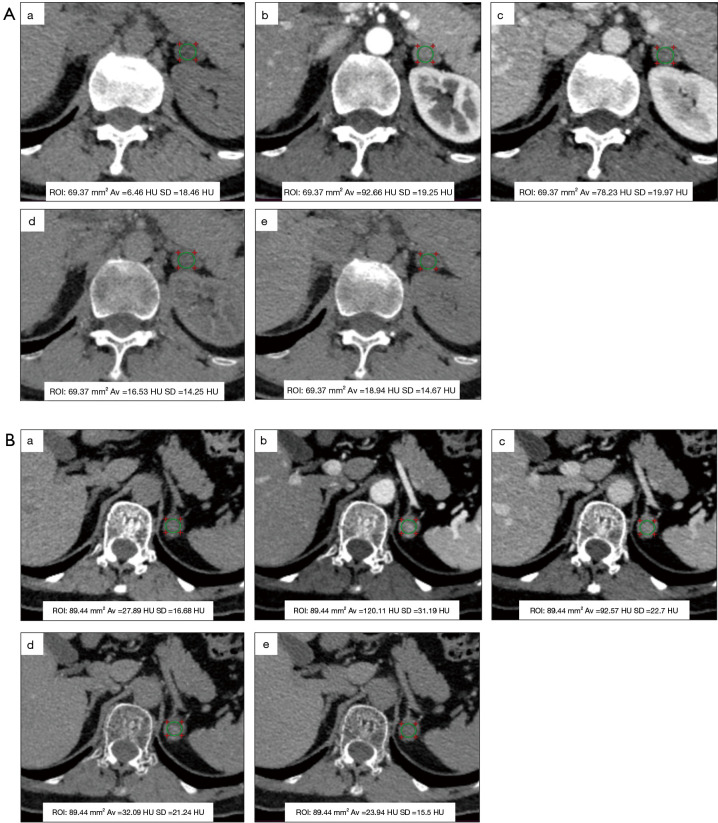

{"title":"肾上腺腺瘤表征的双层光谱检测器计算机断层扫描:辐射剂量减少和多相虚拟非对比成像与真实非对比成像的定量一致。","authors":"Deying Wen, Wen Li, Ling Zhao, Qinglin Du, Xiaoyu Tong, Ailin Liang, Tengxin Wang, Zheng Li, Xiaodi Zhang, Haiwei Liu, Yan Ren, Jiayu Sun","doi":"10.21037/qims-2025-854","DOIUrl":null,"url":null,"abstract":"<p><strong>Background: </strong>Computed tomography (CT) is the preferred imaging modality for evaluating adrenal lesions; however, the associated radiation exposure remains a significant concern. Dual-layer spectral detector CT (SDCT)-derived virtual noncontrast (VNC) images may reduce radiation exposure by eliminating dedicated noncontrast scans, yet their agreement with true noncontrast (TNC) imaging remains debated. This study aimed to quantitatively evaluate the agreement and image quality of VNC images [reconstructed from the arterial phase (VNCa) and portal venous phase (VNCp)] compared to TNC images in adrenal adenomas stratified by lipid content, and to assess the radiation dose reduction.</p><p><strong>Methods: </strong>A total of 103 patients with adrenal adenomas treated at the Adrenal Disease Center of West China Hospital of Sichuan University between March 2023 and September 2024 were enrolled in this prospective study. All patients underwent dual-layer SDCT examination, including TNC and arterial and venous phase scans. VNC images were reconstructed from contrast-enhanced phases. Objective metrics, including CT attenuation value [Hounsfield units (HU)], noise (standard deviation), signal-to-noise ratio (SNR), contrast-to-noise ratio, and absolute attenuation error, and subjective image quality were compared. Interobserver agreement was assessed through the calculation of interclass correlation coefficients. For objective and subjective comparisons between TNC and VNC images, statistical analyses were performed with paired <i>t</i>-tests and Wilcoxon signed-rank tests. The radiation dose with and without TNC was calculated.</p><p><strong>Results: </strong>This study included 103 patients (48 males and 55 females) with a mean age of 51.33±12.55 years. A total of 123 adrenal adenomas were identified, including 28 lipid-rich adenomas and 95 lipid-poor adenomas. For lipid-poor adenomas, VNC and TNC images showed excellent agreement in CT attenuation values (P>0.05), and compared to VNCp images, VNCa images exhibited significantly lower noise (17.44±3.39 <i>vs.</i> 18.64±2.91 HU; P<0.001) and higher SNR (1.68±0.76 <i>vs.</i> 1.55±0.67; P<0.001). In lipid-rich adenomas, VNC images overestimated CT attenuation, showing high absolute attenuation errors (VNCaerror: 9.92±6.49 HU; VNCperror: 8.50±5.17 HU), although these remained within the acceptable threshold of ≤10 HU. In the subjective scores of image quality, TNC images outperformed VNC images [TNC: median 5, interquartile range (IQR) 5-5; VNC: median 5 (IQR 4-5); P<0.001], although VNC scores remained high. No significant statistical difference was observed between the VNCa and VNCp scores (P>0.05). For most of the surrounding nonadenoma tissues, VNC and TNC images demonstrated good agreement, with attenuation differences consistently within ≤10 HU. Replacing TNC images with VNCa images could reduce the effective dose by approximately 32.63% for lipid-poor adenomas.</p><p><strong>Conclusions: </strong>Our findings suggest that for lipid-poor adenomas, VNCa demonstrates high agreement with TNC and provides superior image quality, supporting its use as a TNC substitute for reduced radiation dose. For lipid-rich adenomas, VNC should be applied with caution due to the potential risk of attenuation overestimation. Subtype classification remains essential in such studies.</p>","PeriodicalId":54267,"journal":{"name":"Quantitative Imaging in Medicine and Surgery","volume":"15 9","pages":"7935-7950"},"PeriodicalIF":2.3000,"publicationDate":"2025-09-01","publicationTypes":"Journal Article","fieldsOfStudy":null,"isOpenAccess":false,"openAccessPdf":"https://www.ncbi.nlm.nih.gov/pmc/articles/PMC12397641/pdf/","citationCount":"0","resultStr":"{\"title\":\"Dual-layer spectral detector computed tomography for adrenal adenoma characterization: radiation dose reduction and quantitative agreement of multiphase virtual noncontrast with true noncontrast imaging.\",\"authors\":\"Deying Wen, Wen Li, Ling Zhao, Qinglin Du, Xiaoyu Tong, Ailin Liang, Tengxin Wang, Zheng Li, Xiaodi Zhang, Haiwei Liu, Yan Ren, Jiayu Sun\",\"doi\":\"10.21037/qims-2025-854\",\"DOIUrl\":null,\"url\":null,\"abstract\":\"<p><strong>Background: </strong>Computed tomography (CT) is the preferred imaging modality for evaluating adrenal lesions; however, the associated radiation exposure remains a significant concern. Dual-layer spectral detector CT (SDCT)-derived virtual noncontrast (VNC) images may reduce radiation exposure by eliminating dedicated noncontrast scans, yet their agreement with true noncontrast (TNC) imaging remains debated. This study aimed to quantitatively evaluate the agreement and image quality of VNC images [reconstructed from the arterial phase (VNCa) and portal venous phase (VNCp)] compared to TNC images in adrenal adenomas stratified by lipid content, and to assess the radiation dose reduction.</p><p><strong>Methods: </strong>A total of 103 patients with adrenal adenomas treated at the Adrenal Disease Center of West China Hospital of Sichuan University between March 2023 and September 2024 were enrolled in this prospective study. All patients underwent dual-layer SDCT examination, including TNC and arterial and venous phase scans. VNC images were reconstructed from contrast-enhanced phases. Objective metrics, including CT attenuation value [Hounsfield units (HU)], noise (standard deviation), signal-to-noise ratio (SNR), contrast-to-noise ratio, and absolute attenuation error, and subjective image quality were compared. Interobserver agreement was assessed through the calculation of interclass correlation coefficients. For objective and subjective comparisons between TNC and VNC images, statistical analyses were performed with paired <i>t</i>-tests and Wilcoxon signed-rank tests. The radiation dose with and without TNC was calculated.</p><p><strong>Results: </strong>This study included 103 patients (48 males and 55 females) with a mean age of 51.33±12.55 years. A total of 123 adrenal adenomas were identified, including 28 lipid-rich adenomas and 95 lipid-poor adenomas. For lipid-poor adenomas, VNC and TNC images showed excellent agreement in CT attenuation values (P>0.05), and compared to VNCp images, VNCa images exhibited significantly lower noise (17.44±3.39 <i>vs.</i> 18.64±2.91 HU; P<0.001) and higher SNR (1.68±0.76 <i>vs.</i> 1.55±0.67; P<0.001). In lipid-rich adenomas, VNC images overestimated CT attenuation, showing high absolute attenuation errors (VNCaerror: 9.92±6.49 HU; VNCperror: 8.50±5.17 HU), although these remained within the acceptable threshold of ≤10 HU. In the subjective scores of image quality, TNC images outperformed VNC images [TNC: median 5, interquartile range (IQR) 5-5; VNC: median 5 (IQR 4-5); P<0.001], although VNC scores remained high. No significant statistical difference was observed between the VNCa and VNCp scores (P>0.05). For most of the surrounding nonadenoma tissues, VNC and TNC images demonstrated good agreement, with attenuation differences consistently within ≤10 HU. Replacing TNC images with VNCa images could reduce the effective dose by approximately 32.63% for lipid-poor adenomas.</p><p><strong>Conclusions: </strong>Our findings suggest that for lipid-poor adenomas, VNCa demonstrates high agreement with TNC and provides superior image quality, supporting its use as a TNC substitute for reduced radiation dose. For lipid-rich adenomas, VNC should be applied with caution due to the potential risk of attenuation overestimation. Subtype classification remains essential in such studies.</p>\",\"PeriodicalId\":54267,\"journal\":{\"name\":\"Quantitative Imaging in Medicine and Surgery\",\"volume\":\"15 9\",\"pages\":\"7935-7950\"},\"PeriodicalIF\":2.3000,\"publicationDate\":\"2025-09-01\",\"publicationTypes\":\"Journal Article\",\"fieldsOfStudy\":null,\"isOpenAccess\":false,\"openAccessPdf\":\"https://www.ncbi.nlm.nih.gov/pmc/articles/PMC12397641/pdf/\",\"citationCount\":\"0\",\"resultStr\":null,\"platform\":\"Semanticscholar\",\"paperid\":null,\"PeriodicalName\":\"Quantitative Imaging in Medicine and Surgery\",\"FirstCategoryId\":\"3\",\"ListUrlMain\":\"https://doi.org/10.21037/qims-2025-854\",\"RegionNum\":2,\"RegionCategory\":\"医学\",\"ArticlePicture\":[],\"TitleCN\":null,\"AbstractTextCN\":null,\"PMCID\":null,\"EPubDate\":\"2025/8/14 0:00:00\",\"PubModel\":\"Epub\",\"JCR\":\"Q2\",\"JCRName\":\"RADIOLOGY, NUCLEAR MEDICINE & MEDICAL IMAGING\",\"Score\":null,\"Total\":0}","platform":"Semanticscholar","paperid":null,"PeriodicalName":"Quantitative Imaging in Medicine and Surgery","FirstCategoryId":"3","ListUrlMain":"https://doi.org/10.21037/qims-2025-854","RegionNum":2,"RegionCategory":"医学","ArticlePicture":[],"TitleCN":null,"AbstractTextCN":null,"PMCID":null,"EPubDate":"2025/8/14 0:00:00","PubModel":"Epub","JCR":"Q2","JCRName":"RADIOLOGY, NUCLEAR MEDICINE & MEDICAL IMAGING","Score":null,"Total":0}

背景:计算机断层扫描(CT)是评估肾上腺病变的首选成像方式;然而,相关的辐射暴露仍然是一个重大问题。双层光谱探测器CT (SDCT)衍生的虚拟非对比(VNC)图像可以通过消除专用的非对比扫描来减少辐射暴露,但它们与真正的非对比(TNC)成像的一致性仍存在争议。本研究旨在定量评价按脂质含量分层的肾上腺腺瘤的VNC图像[由动脉期(VNCa)和门静脉期(VNCp)重建]与TNC图像的一致性和图像质量,并评估辐射剂量的减少。方法:本前瞻性研究纳入2023年3月至2024年9月在四川大学华西医院肾上腺疾病中心接受治疗的肾上腺腺瘤患者103例。所有患者均行双层SDCT检查,包括TNC期和动、静脉期扫描。从对比度增强阶段重建VNC图像。比较客观指标,包括CT衰减值[Hounsfield units (HU)]、噪声(标准差)、信噪比(SNR)、对比噪声比、绝对衰减误差,以及主观图像质量。通过计算类间相关系数来评估观察者间的一致性。对于TNC和VNC图像的客观和主观比较,采用配对t检验和Wilcoxon符号秩检验进行统计分析。计算了有无TNC的辐射剂量。结果:103例患者(男48例,女55例),平均年龄51.33±12.55岁。共发现123例肾上腺腺瘤,其中富脂腺瘤28例,贫脂腺瘤95例。对于低脂腺瘤,VNC与TNC影像在CT衰减值上表现出极好的一致性(P < 0.05),且与VNCp影像相比,VNCa影像表现出更低的噪声(17.44±3.39 vs. 18.64±2.91 HU; Pvs. 1.55±0.67;P0.05)。对于大多数周围非腺瘤组织,VNC和TNC图像表现出良好的一致性,衰减差异在≤10 HU范围内一致。对于脂质贫乏的腺瘤,用VNCa图像代替TNC图像可使有效剂量降低约32.63%。结论:我们的研究结果表明,对于脂质贫乏的腺瘤,VNCa与TNC表现出高度的一致性,并提供了优越的图像质量,支持其作为TNC替代降低辐射剂量。对于富含脂质的腺瘤,VNC应用应谨慎,因为衰减高估的潜在风险。亚型分类在这类研究中仍然是必不可少的。

Methods: A total of 103 patients with adrenal adenomas treated at the Adrenal Disease Center of West China Hospital of Sichuan University between March 2023 and September 2024 were enrolled in this prospective study. All patients underwent dual-layer SDCT examination, including TNC and arterial and venous phase scans. VNC images were reconstructed from contrast-enhanced phases. Objective metrics, including CT attenuation value [Hounsfield units (HU)], noise (standard deviation), signal-to-noise ratio (SNR), contrast-to-noise ratio, and absolute attenuation error, and subjective image quality were compared. Interobserver agreement was assessed through the calculation of interclass correlation coefficients. For objective and subjective comparisons between TNC and VNC images, statistical analyses were performed with paired t-tests and Wilcoxon signed-rank tests. The radiation dose with and without TNC was calculated.

Results: This study included 103 patients (48 males and 55 females) with a mean age of 51.33±12.55 years. A total of 123 adrenal adenomas were identified, including 28 lipid-rich adenomas and 95 lipid-poor adenomas. For lipid-poor adenomas, VNC and TNC images showed excellent agreement in CT attenuation values (P>0.05), and compared to VNCp images, VNCa images exhibited significantly lower noise (17.44±3.39 vs. 18.64±2.91 HU; P<0.001) and higher SNR (1.68±0.76 vs. 1.55±0.67; P<0.001). In lipid-rich adenomas, VNC images overestimated CT attenuation, showing high absolute attenuation errors (VNCaerror: 9.92±6.49 HU; VNCperror: 8.50±5.17 HU), although these remained within the acceptable threshold of ≤10 HU. In the subjective scores of image quality, TNC images outperformed VNC images [TNC: median 5, interquartile range (IQR) 5-5; VNC: median 5 (IQR 4-5); P<0.001], although VNC scores remained high. No significant statistical difference was observed between the VNCa and VNCp scores (P>0.05). For most of the surrounding nonadenoma tissues, VNC and TNC images demonstrated good agreement, with attenuation differences consistently within ≤10 HU. Replacing TNC images with VNCa images could reduce the effective dose by approximately 32.63% for lipid-poor adenomas.